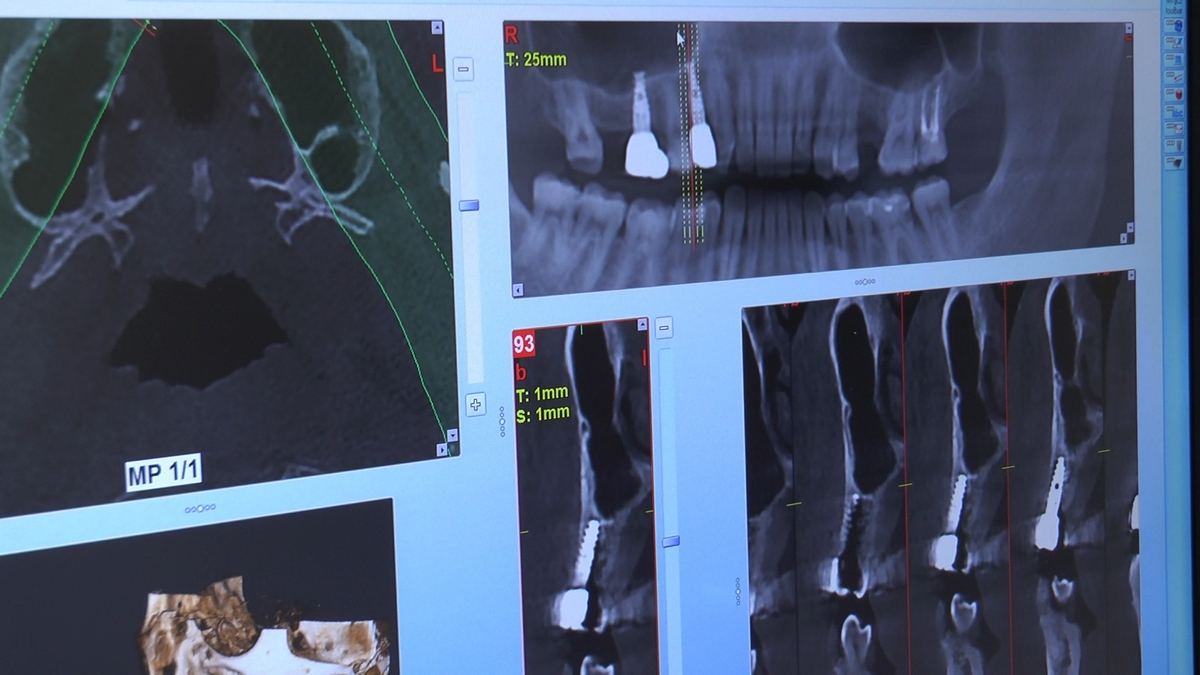

W trakcje dwóch dni zabiegowych, piątek i sobota, 5 i 6 października 2018 roku, lekarze uczestniczący w 6 Sesji VI Sezonu, wykonali wiele zabiegów o wysokim stopniu trudności. Przeprowadzili je pod kierunkiem Mentorów Instytutu Vivadental – dr n.med. Violetty Szycik, dr n.med. Magdaleny Kisłowskiej-Syryczyńskiej oraz dr Małgorzaty Piotrowskiej.

Wprowadziliśmy łącznie 25 implantów w tym wykonaliśmy:

dwa zabiegi All- on -4 / jeden w szczęce, jeden w żuchwie/ z usunięciem zębów i natychmiastową implantacją oraz natychmiastową odbudową protetyczną

jeden zabieg sinus lift otwarty